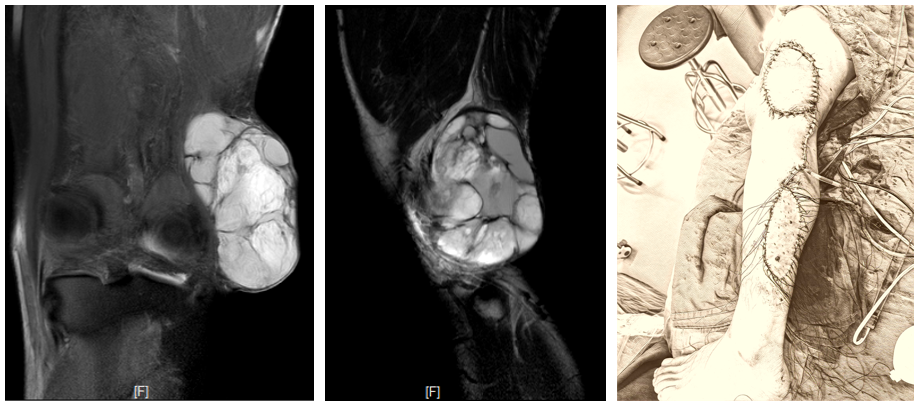

案例一 左上臂粘液纤维肉瘤(术后复发),行肿瘤扩大性切除,使用带血管蒂的背阔肌皮瓣转移作软组织修复。

案例三 左膝外侧粘液纤维肉瘤(术后复发),行左膝肉瘤扩大切除,膝关节外侧软组织缺损,采用腓肠肌外侧肌皮瓣转移和取皮植皮修复创面。